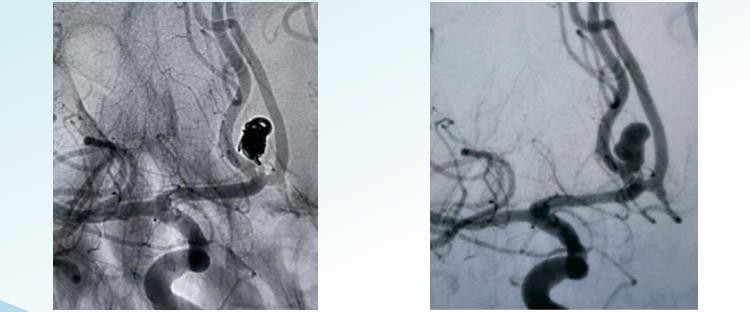

RenowacjaTMOdłączane cewki 3D

RenowacjaTMSpiralne odłączane cewki